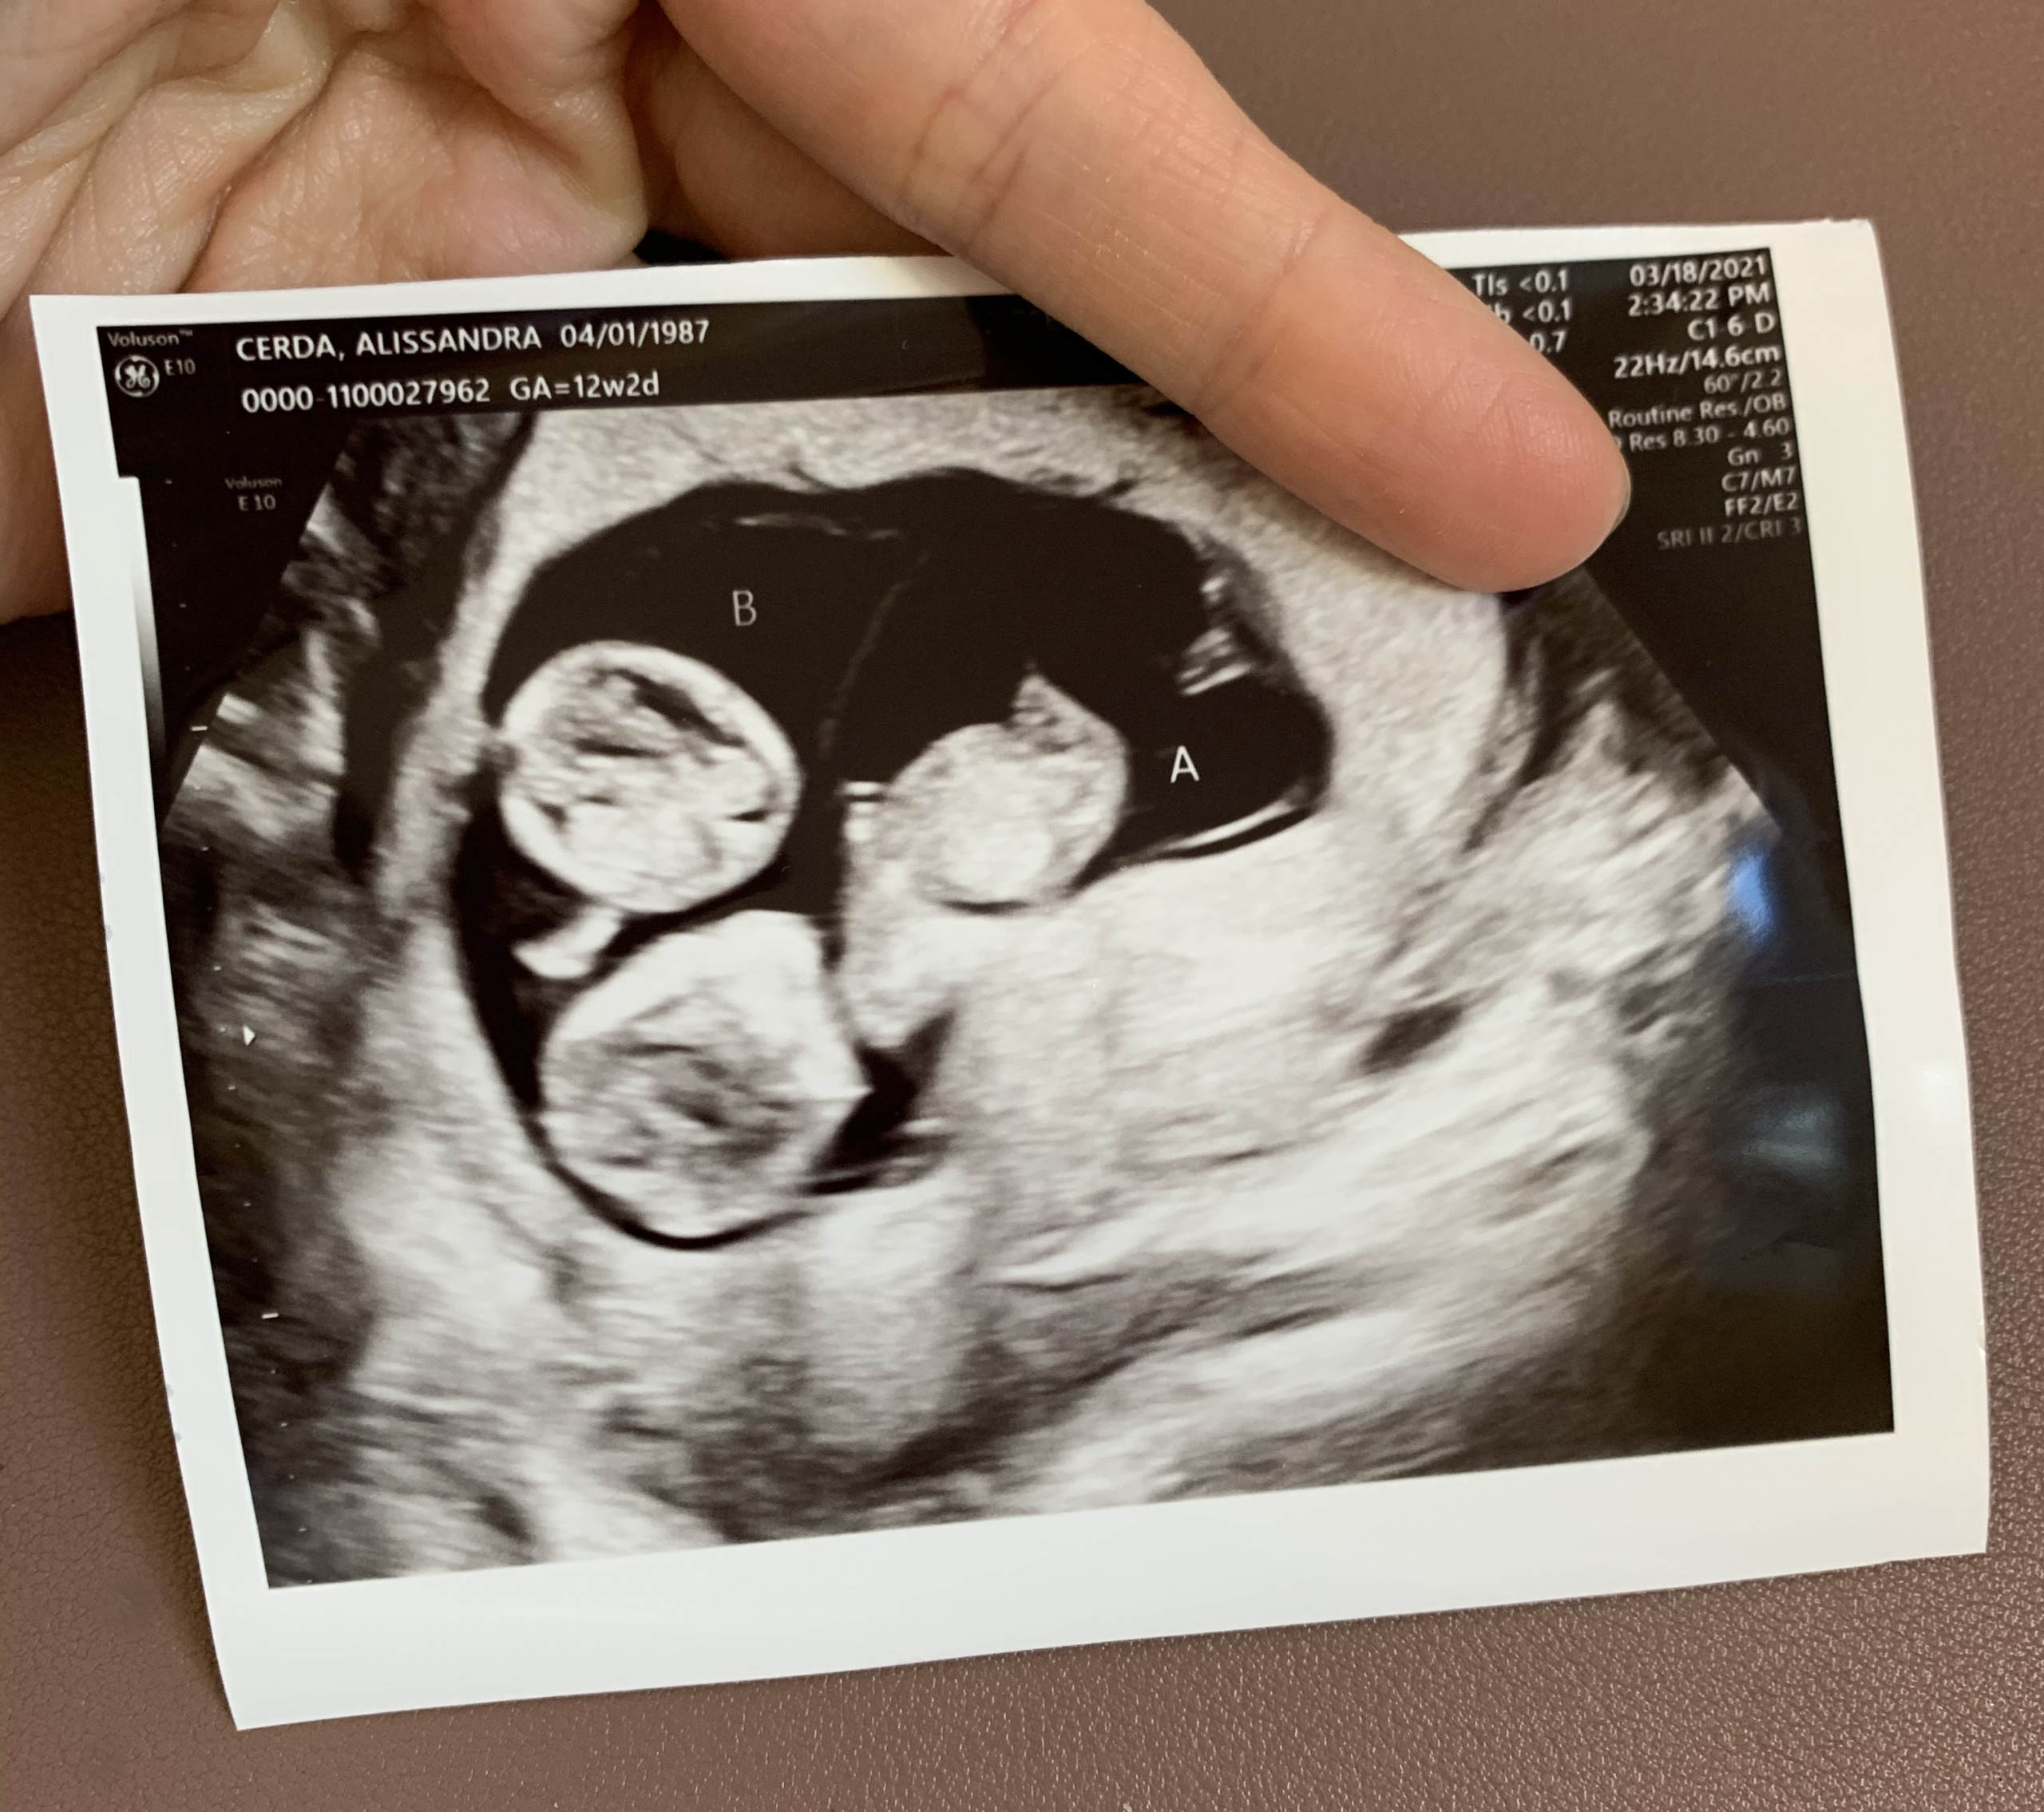

Identical Twins Ultrasound 12 Weeks

Identical Twins Ultrasound 12 Weeks How To Tell Identical Twins From Ultrasound Identical twins share a placenta and all or part of the. Indicates monochorionic twins, with thin membrane and absence of thickening at membrane insertion site. However, identical (monozygotic) twins might share an amniotic sac or have separate sacs depending on how early the egg. A single placental mass does not rule out dichorionic twins. Sometimes twins develop their own individual. How To Tell Identical Twins From Ultrasound.